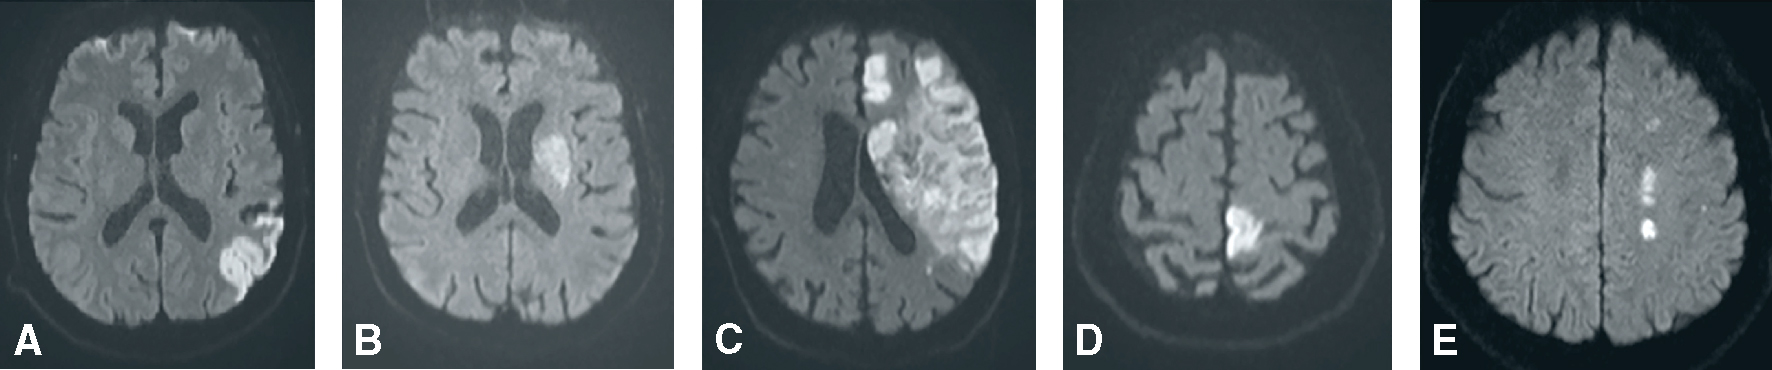

Fig. 28.4 Figure Infarctus de la circulation antérieure.

A. Infarctus sylvien superficiel (IRM séquence de diffusion). B. Infarctus sylvien profond (IRM séquence diffusion). C. Infarctus sylvien total (IRM séquence diffusion). D. Infarctus cérébral antérieur (IRM séquence diffusion). E. Infarctus jonctionnel (IRM séquence diffusion).

Infarctus cérébral de l’artère cérébrale moyenne (ACM) superficiel (fig. 28.4A)

Infarctus cérébral de l’ACM territoire profond (fig. 28.4B)

Infarctus cérébral de l’ACM total (fig. 28.4C)

b 518Infarctus cérébral antérieur (fig. 28.4D)

a Infarctus cérébral postérieur (fig. 28.5A et B)

Fig. 28.5 Figure Infarctus de la circulation postérieure. IRM séquence de diffusion.

A. Infarctus cérébral postérieur superficiel droit et gauche. B. Infarctus thalamique gauche. C. Infarctus de perforante du pont (protubéranciel) gauche. D. Infarctus cérébelleux gauche. E. Infarctus de la fossette latérale du bulbe (syndrome de Wallenberg) droit.